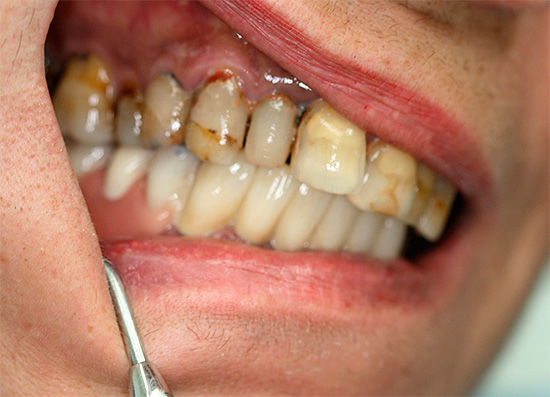

Deve-se ter em mente que o conceito de "implantação basal", como tal, hoje é coisa do passado. Existe um protocolo de carregamento imediato, que inclui várias tecnologias para restauração dentária, dependendo do quadro clínico. É adequado para restaurações simples e múltiplas, incluindo a ausência completa de dentes - um exemplo correspondente é mostrado nas fotografias abaixo:

É por isso que você não deve confiar cegamente na publicidade de clínicas odontológicas que oferecem implante basal - você deve necessariamente pesar os prós e contras, verificar os atestados médicos e observar os resultados de suas habilidades práticas (por exemplo, examine fotos com exemplos mostrando a cavidade oral dos pacientes antes e depois do tratamento) .